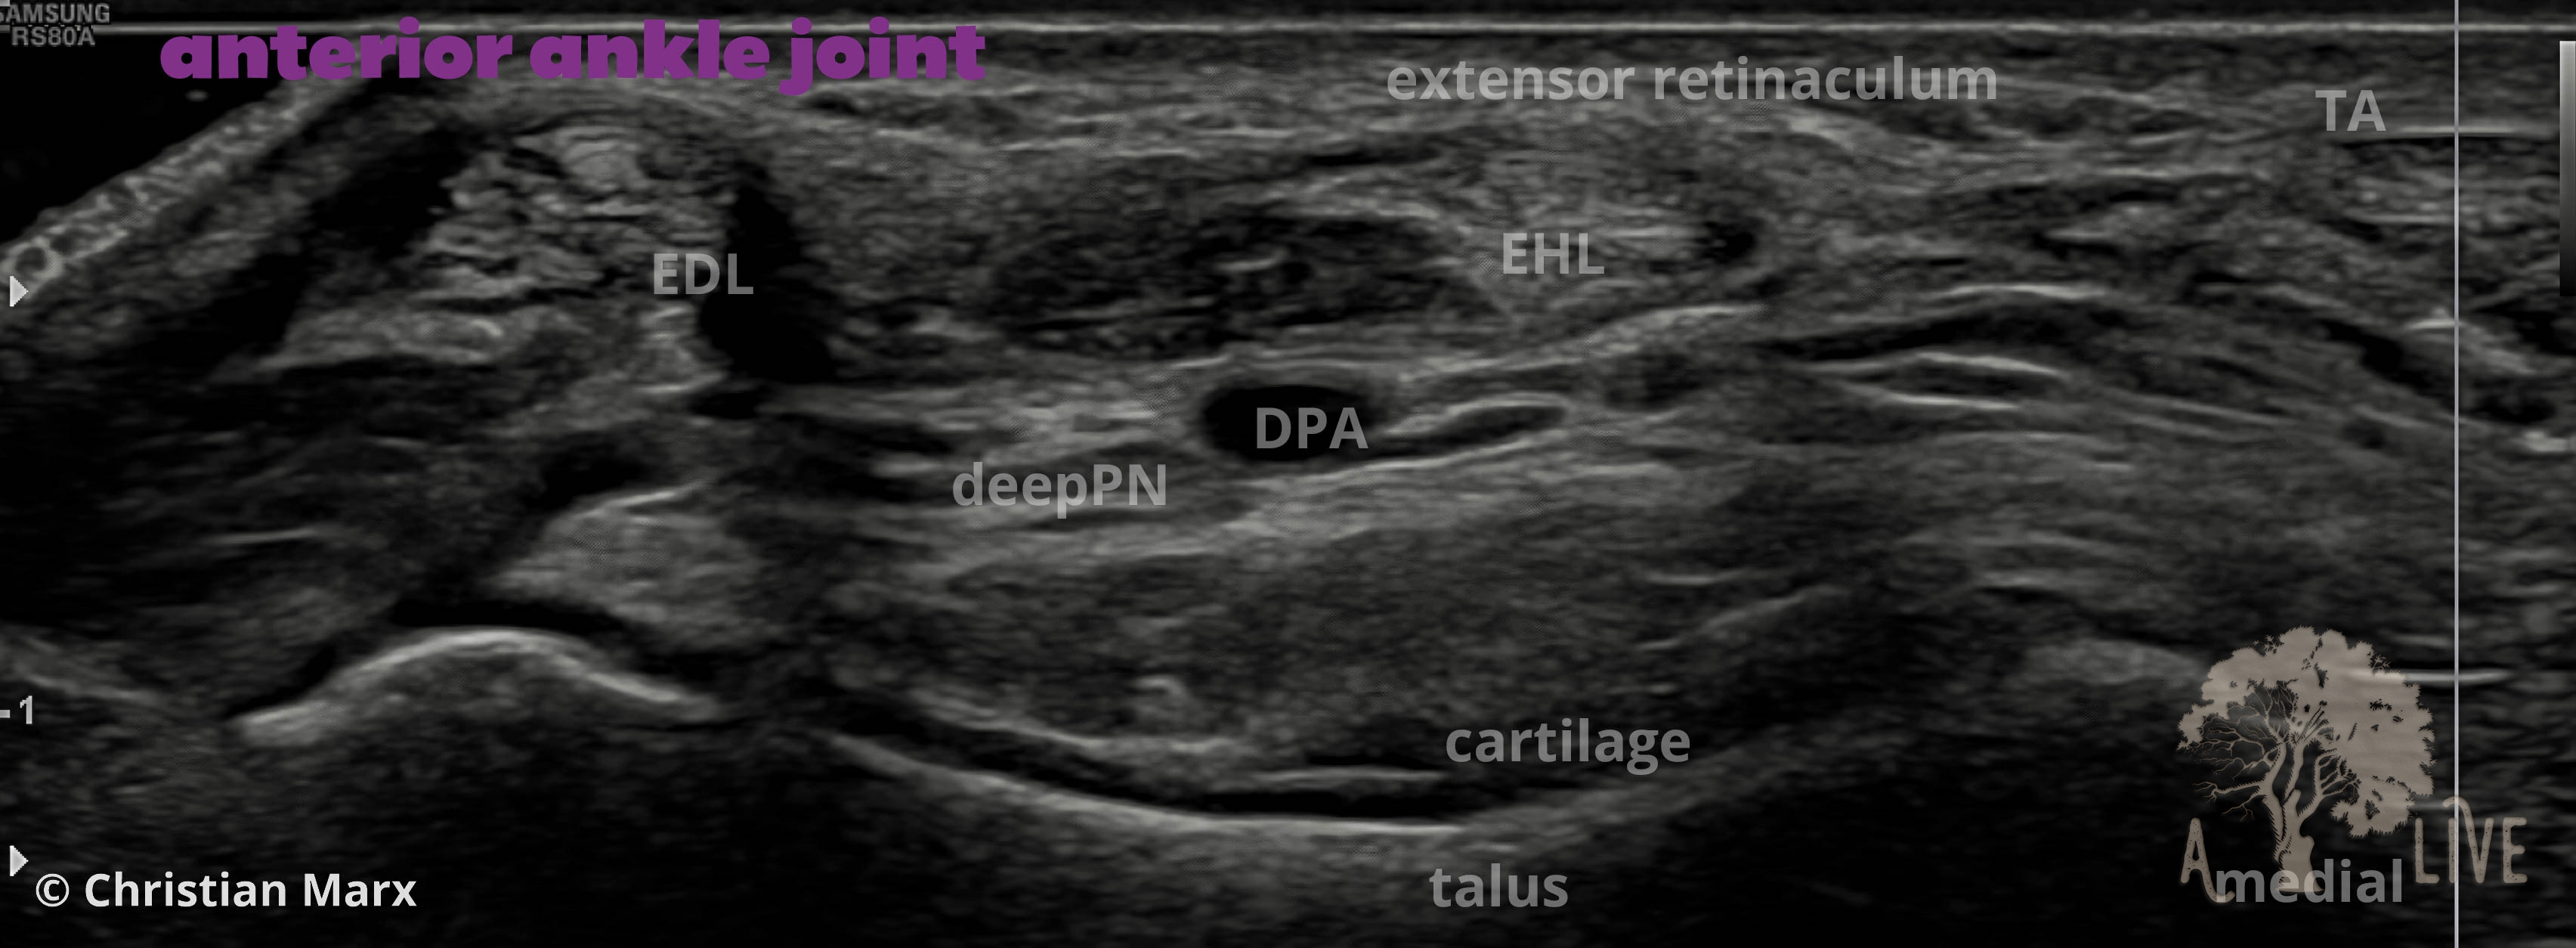

foot tibiotalar (ankle) joint